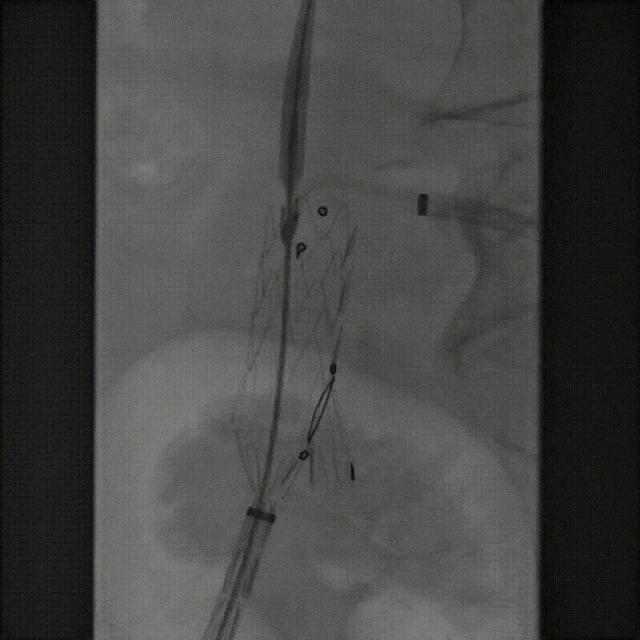

该技术主要适用于采用旋转式释放机制的支架。其核心操作步骤为:在主体支架释放出前2-3节后,轻微松开支架,然后反复反向旋转并上推输送鞘。 这一动作能促使已释放的近端支架段在瘤颈处产生可控的“堆叠”效应,从而更好地顺应瘤颈的弯曲形态,尤其是在大弯侧实现更紧密的贴壁,有效拓展了功能性密封区。

案例一(巨大成角瘤颈):患者瘤颈虽长但呈90度成角。在完成髂动脉重建后,采用Reverse技术释放主体支架。术中造影显示,支架完美贴合扭曲的血管大弯侧,术后一月复查CTA,原有的少量内漏已完全消失。

案例二(短瘤颈+梯形瘤颈):患者近端瘤颈长度不足1cm,且伴有大量附壁血栓。选用适当oversize的支架,结合Reverse技术释放,支架主体自动“寻找”并适应最佳的贴附区域,最终造影显示无明确内漏。

截至目前,采用Reverse技术处理不良瘤颈的初步经验(21例)显示,术中发生明显I型内漏仅3例,其中2例经弹簧圈栓塞处理,1例在随访中自行消失。这表明Reverse技术在处理不良瘤颈时,是一种安全、有效且能显著减少内漏发生的手段。